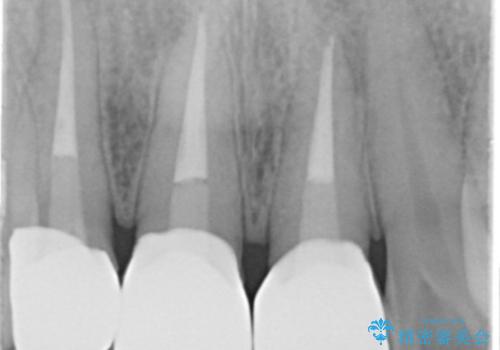

視診・X線検査・歯周組織検査より下記のような問題が列挙され、長期的な予後を見込むために一つづつ問題の解決を計ります。

・不十分な根管治療 →マイクロスコープを用いる精密根管医療

・歯の変色 →ジルコニアクラウンの製作

・歯肉縁下カリエス →部分矯正による歯の挺出・歯周外科

歯の挺出を行ったことで歯ぐきの腫れも改善され、安定した歯周環境下でのセラミッククラウン治療を行うことができました。